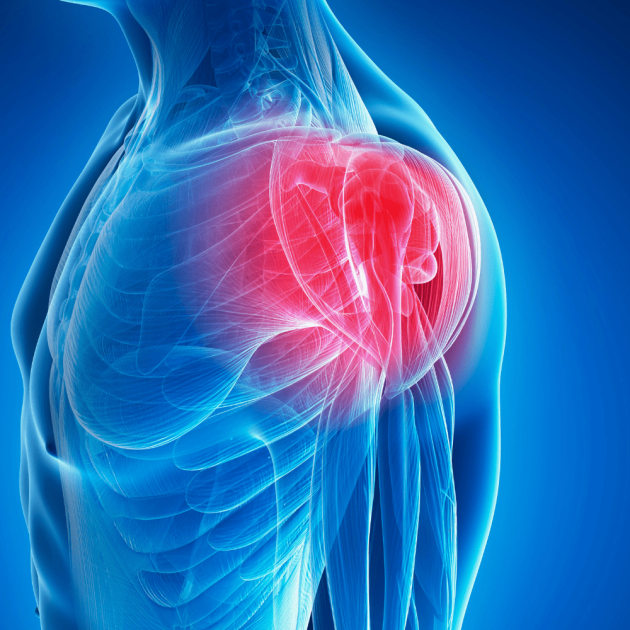

Upper Body